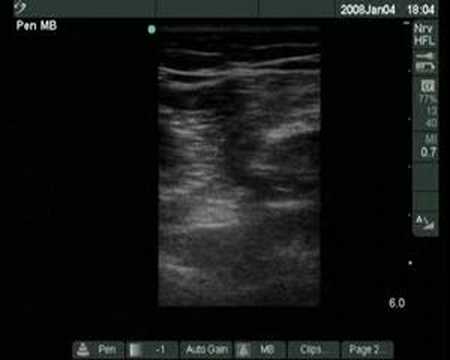

Pinched Nerve Ultrasound

What Is A pinched nerve: Oldsmar Chiropractor Dr. Bode - YouTube